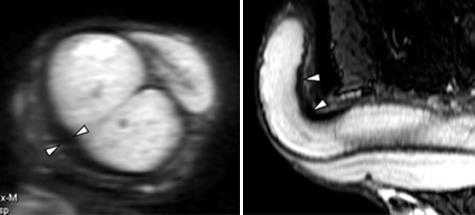

Опухоли яичек наиболее часто встречается в возрасте 15-40 лет.

Небольшое правостороннее гидроцеле (*). Септальное строение опухоли, выявляемое при внутривенном контрастировании.

Левосторонняя семинома с инвазией левого семенного канатика.